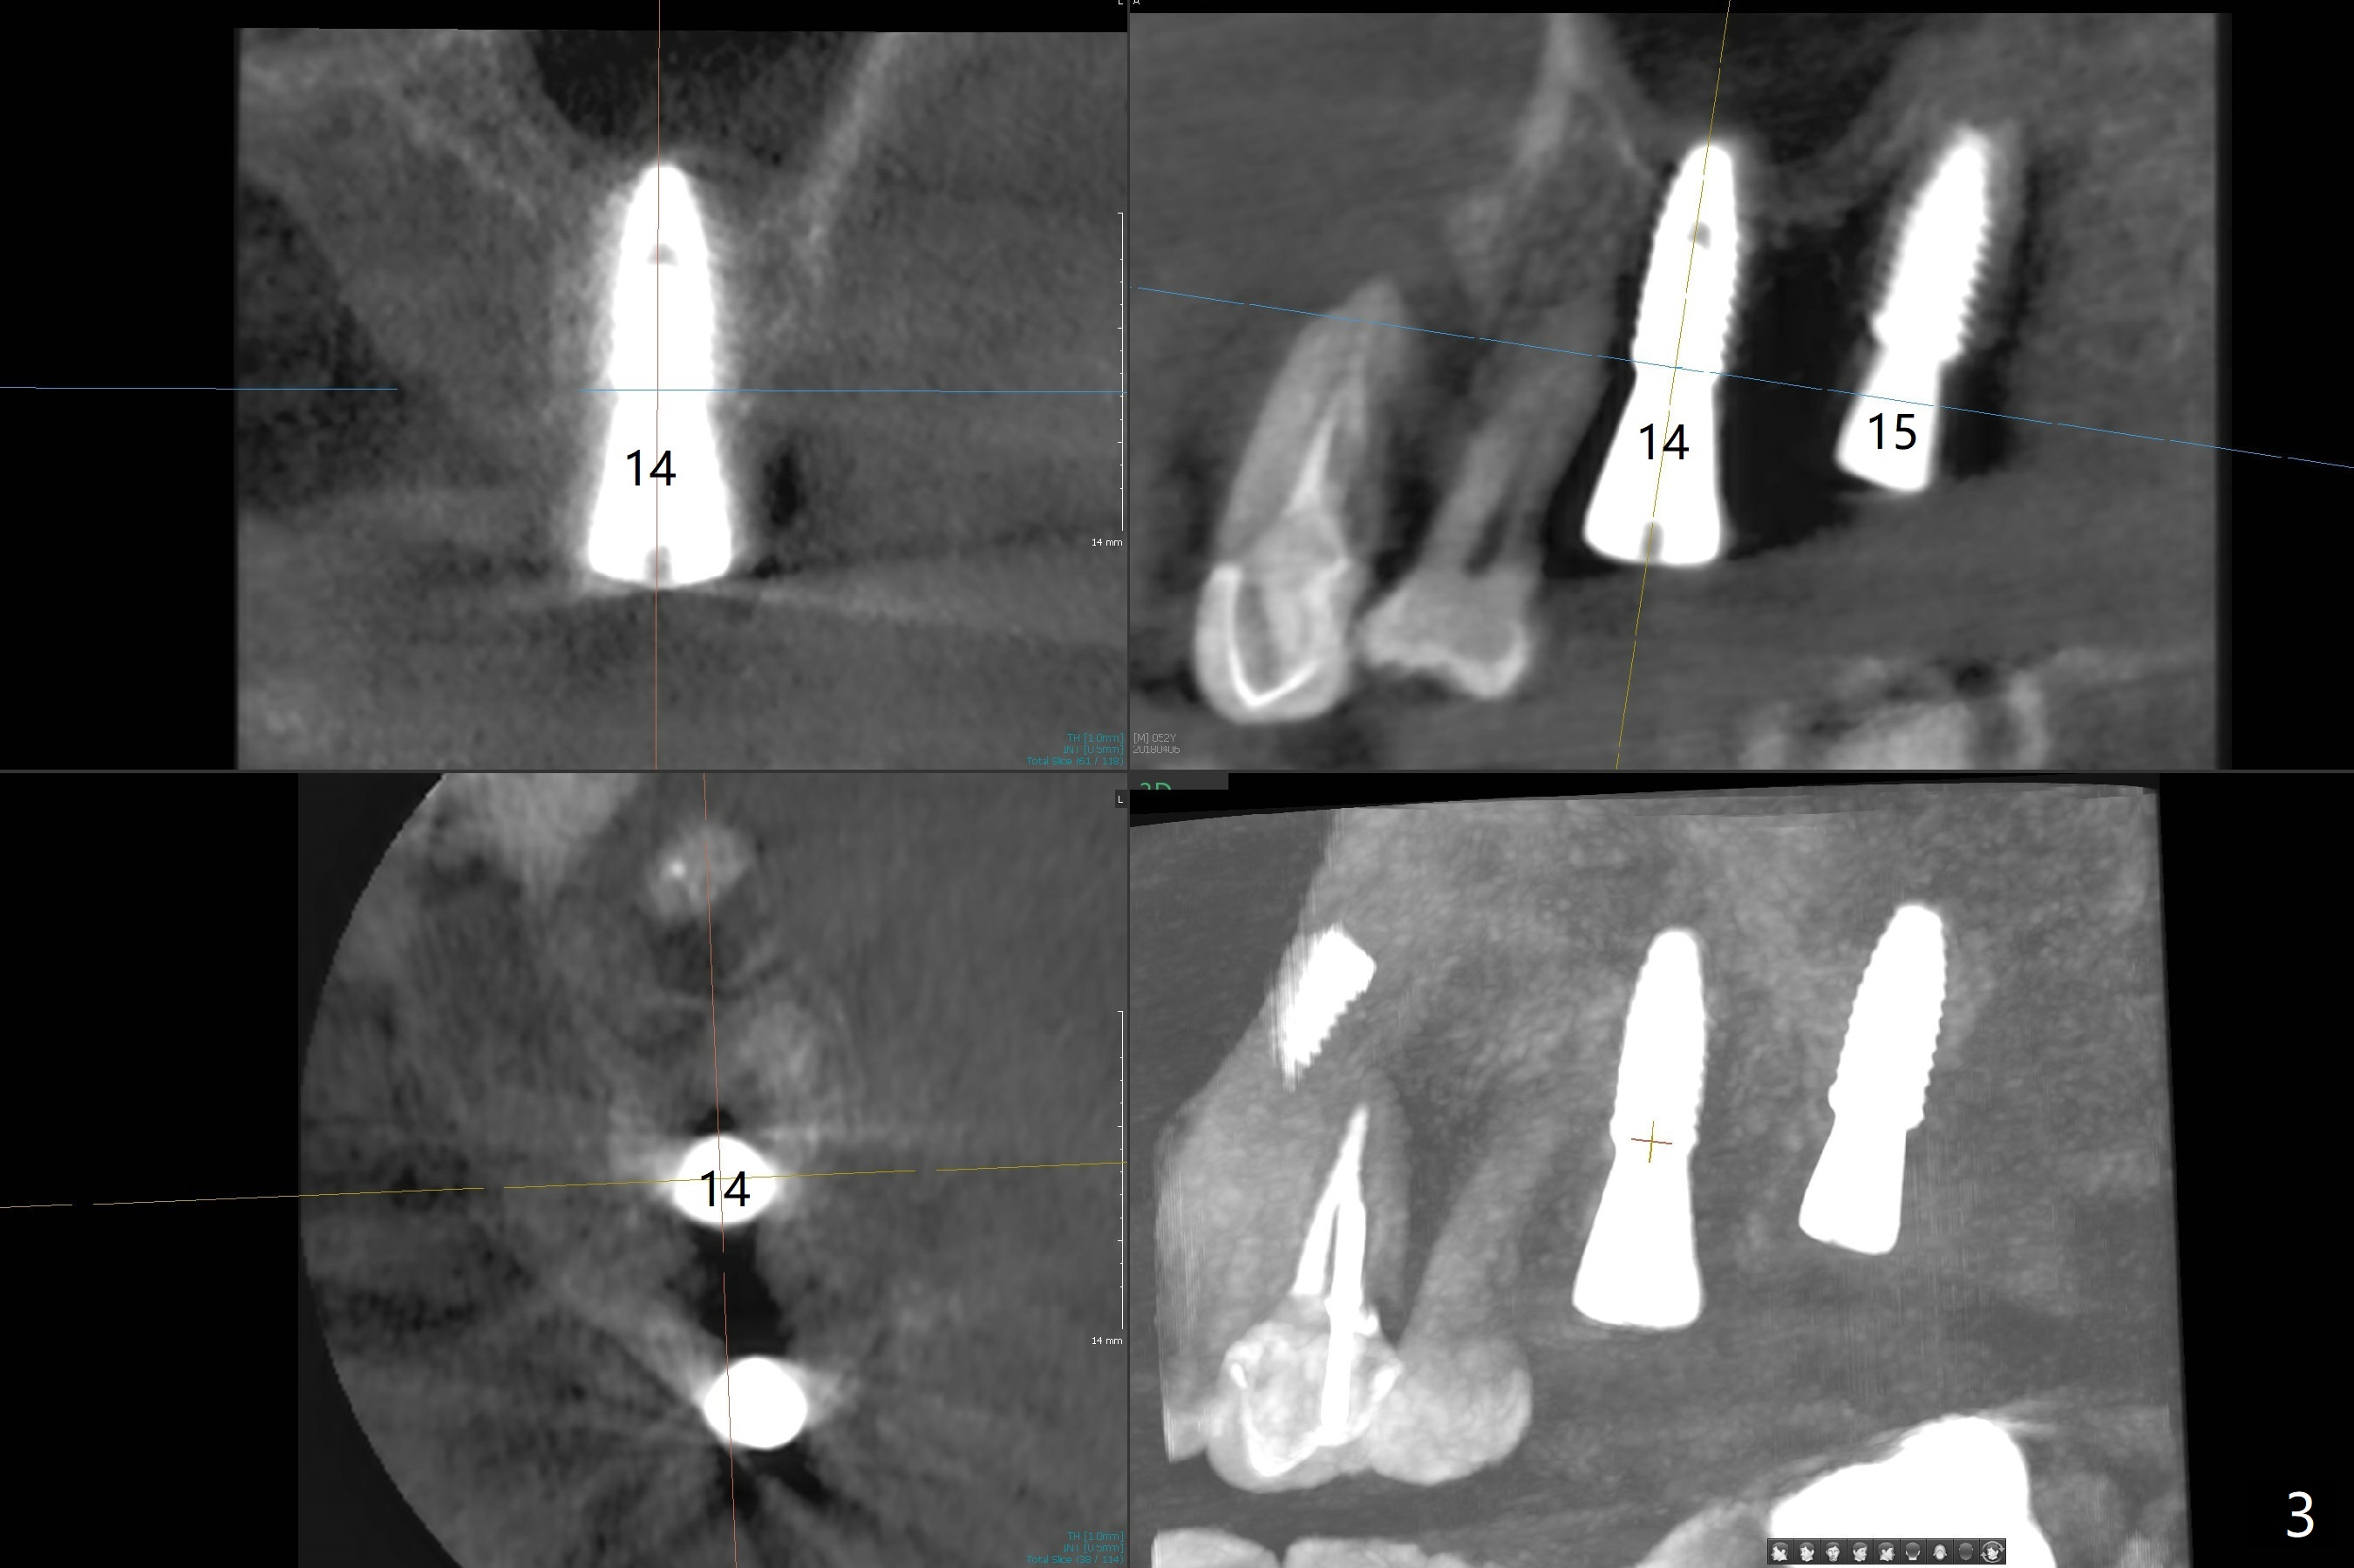

Immediately postop PA (Fig.1) and panoramic X-ray (Fig.2) show that the implant at #14 is close to the root of the tooth #13.  Clinic exam and CBCT (Fig.3,4) demonstrate a reasonable separation.  The trajectory of #14 osteotomy may be altered while using 2.8 mm round drill for 7-9 mm for sinus lift (free hand).  There is no bone loss 8 months postop (Fig.5).

#15 looks good as planned and #14 seems quite close to the neighboring tooth and quite off from the planed position.